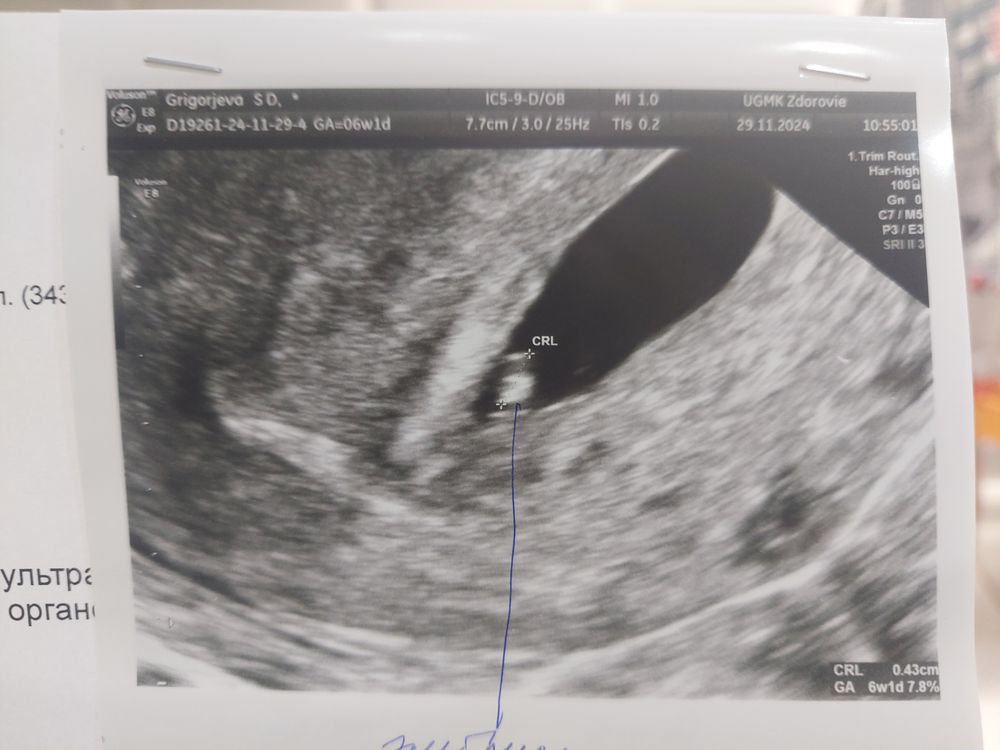

Светланка в Зачатие год Сходила второй раз на узи) УЗИ Увидели сердцебиение, дали послушать ❤️Срок соответствует М, 6 нед 1 день. На 2 фото справа эмбриончик, слева желточный мешочек. Посмотрите еще 20 записей на эту тему Лучший ответ Яна Поздравляю 🙏 29.11.2024 Ответить Отменить Ответить Доминантный фолликул 17 мм Первое узи, эмоции Чаты Беременных Выберите чат: Январята-2026 Февралята-2026 Мартята-2026 Апрелята-2026 Майчата-2026 Июнята-2026 Июлята-2026 Августята-2026